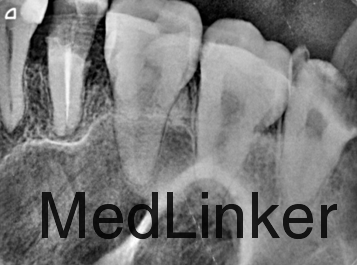

主诉:左上后牙有洞,刷牙出血一年余。 现病史:一年来自觉左上后牙刷牙出血,有大洞。今来诊